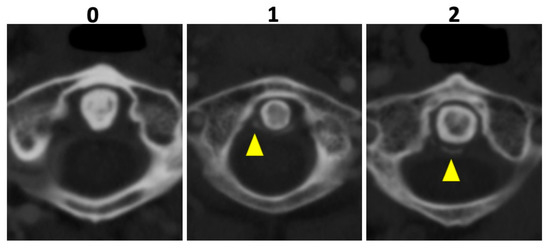

2.4. Image Reading